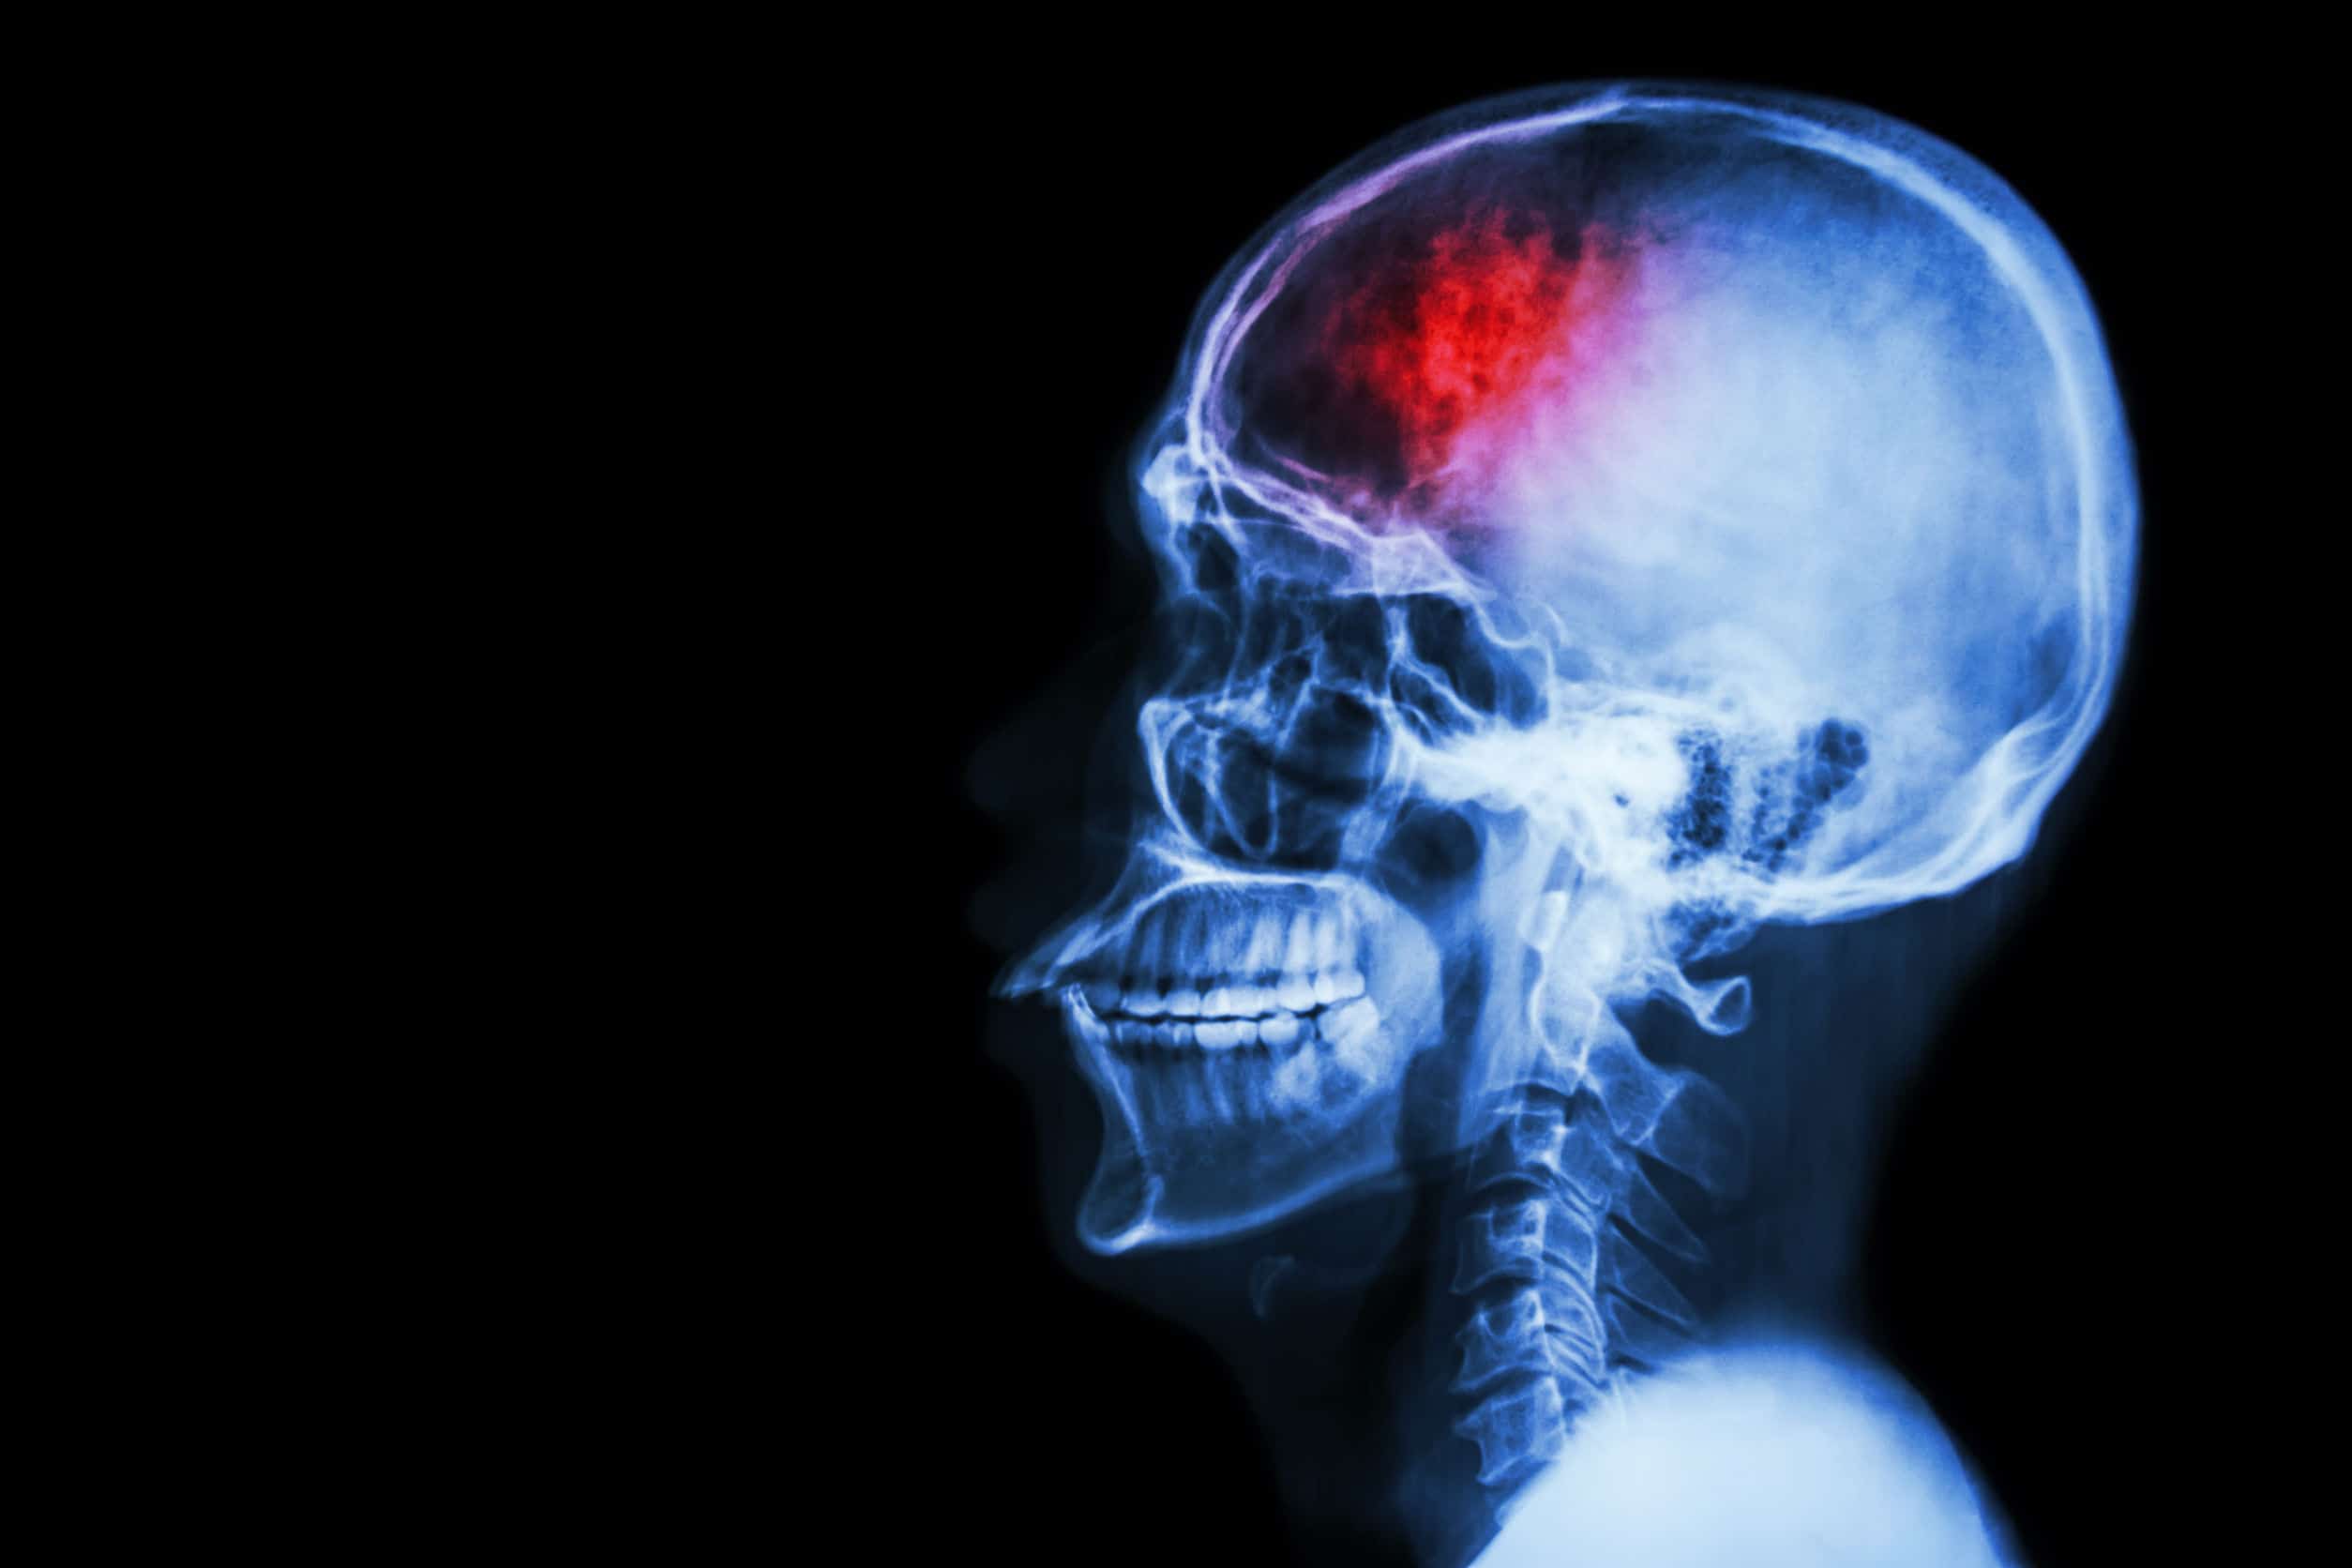

What is CTE Disease? CTE is a degenerative brain disease that is often found in athletes that are involved in contact sports and military veterans. Repetitive brain trauma is a major cause of CTE. The continuous repetition of brain injuries and trauma has been associated with a build-up of an abnormal protein called Tau, as well as degrading brain tissue.

A concussion is caused by a blow to the head or even to the body that can cause the brain and head to move rapidly back and forth. The brain can hit the inside part of the skull, causing severe trauma. Symptoms of a concussion can include problems with coordination, nausea, vomiting, trouble concentrating, and headaches. Sub-concussive head injuries may not show any symptoms. This is defined as a blow to the head that is not severe enough to be medically diagnosed as a concussion. However, it can still have long-term effects on the brain, especially if there are repetitive sub-concussive head injuries.

The diagnosis of CTE disease is not an easy one to make. As of now, doctors can only diagnosis CTE after a person passes away. This allows medical professionals to analyze brain tissue and look for Tau protein, which is associated with CTE. Currently, CTE cannot be diagnosed before death due to the process it takes to analyze brain tissue. The analysis of brain tissues can be a time-consuming process, taking more than a couple of months.